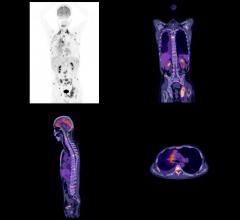

November 20, 2015 — GE Healthcare introduced the Discovery RT, a new advanced radiation therapy planning computed ...